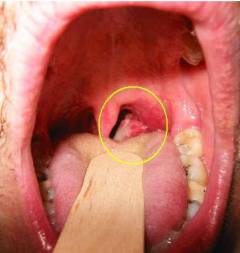

Плоскоклеточный рак гортани

Составляет около 60% всех злокачественных новообразований данного органа. Одинаково часто встречаются обе формы заболевания, однако инфильтративно-язвенный рак характеризуется более быстрым развитием и переходом на соседние органы.

Признаками рака гортани могут быть:

- Затруднение дыхания. В результате роста опухоли просвет гортани может частично перекрываться, что затрудняет прохождение воздуха. В зависимости от расположения опухолевого узла и его размеров может быть затруднен вдох, выдох или и то, и другое.

- Изменение голоса. Возникает при распространении ракового процесса на голосовые связки и может проявляться охриплостью голоса, вплоть до полной его утраты (афонии).

- Боли при глотании. Могут появляться при больших размерах опухолевого узла, сдавливающего глотку и верхний отдел пищевода.

- Кашель. Возникает рефлекторно, в результате механического раздражения стенок гортани. Как правило, не устраняется противокашлевыми лекарственными средствами.

- Кровохаркание. Может возникнуть при разрушении кровеносных сосудов и в результате распада опухоли.

- Ощущение инородного тела в горле.